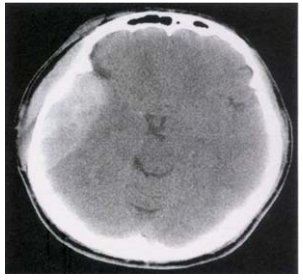

62 38 歲男性,頭部外傷。根據此張 CT 影像,你的診斷是:

(A) Acute epidural hematoma (B)Acute subdural hematoma (C)Acute subarachnoid hemorrhage (D)Acute contusion hemorrhage